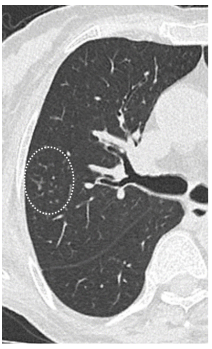

日本一项研究总结了血液系统疾病和造血干细胞移植患者RSV感染的影像学表现,其中一例63岁T淋巴细胞瘤患者感染RSV后症状持续10天,右肺下叶支气管处支气管管壁增厚,经过治疗,情况有所改善(图1)。图2为一例75岁T细胞淋巴瘤患者,起病9天,肺上叶可见小叶中心结节影(图2)。23岁急性粒细胞白血病患者早期影像学表现为多叶段沿支气管束分布的磨玻璃影,随着时间的延长以及治疗的开展,病变密度逐渐增加、皱缩及吸收(图3)。图4为一例78岁慢粒患者,羟基脲治疗,起病1天,影像学可见铺路石征,随着时间的延长,逐渐吸收(图4)

图1  63岁T淋巴细胞瘤患者感染RSV的影像学表现

图源:Intern Med. 2020;59(2):247-252.